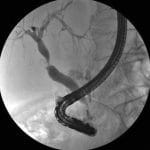

Διαγνωστική ERCP: Η εξέταση ξεκινάει με τη διαγνωστική ERCP για την απεικόνιση της ανατομίας του χολοπαγκρεατικού άξονα και την αποτίμηση των χαρακτηριστικών της στένωσης (θέση, μήκος, διαμόρφωση, μέγεθος). Ο καθετηριασμός της θηλής του Vater μπορεί να είναι δυσχερής ή ακόμα και ανέφικτος στα περιληκυθικά νεοπλάσματα και στον καρκίνο της κεφαλής του παγκρέατος, λόγω της στένωσης του δωδεκαδακτύλου που δεν επιτρέπει την διέλευση του ενδοσκοπίου. Ενδέχεται να απαιτηθεί η προκαταρκτική θηλοτομή (Precut papillotomy) για να επιτευχθεί ο εκλεκτικός καθετηριασμός του χοληδόχου πόρου.

Σφιγκτηροτομή: Μετά τη διαγνωστική ERCP επιτελείται μερική σφιγκτηροτομή σε μήκος 6-8 mm, που διευκολύνει την εισέλευση του συρμάτινου οδηγού, του καθετήρα και της ενδοπρόθεσης στο χοληδόχο πόρο. Με τη σφιγκτηροτομή, αποτρέπεται η έμφραξη του στομίου της εκβολής του παγκρεατικού πόρου από την ίδια την ενδοπρόθεση και έτσι ελαχιστοποιείται ο κίνδυνος της παγκρεατίτιδας. Στη φάση αυτή, λαμβάνονται ιστοτεμαχίδια από την στενεμένη περιοχή με ειδική λαβίδα βιοψίας ή κυτταρολογικό υλικό με καθετήρα, που στην άκρη φέρει ψήκτρα.

Επιλογή ενδοπρόθεσης: Μόλις το άκαμπτο τμήμα του συρμάτινου οδηγού διέλθει κεντρικά της στένωσης, ο πλαστικός καθετήρας προωθείται σε κεντρικότερη θέση, διολισθαίνοντας επί του συρμάτινου οδηγού. Στο σημείο αυτό εγχέεται σκιαγόνος ουσία για την καλύτερη απεικόνιση όλων των κεντρικών χοληφόρων αγγείων πάνω από τη στένωση. Ο πλαστικός καθετήρας μαζί με το συρμάτινο οδηγό συνιστούν μια ενιαία λειτουργική μονάδα και χρησιμεύουν ως οδηγός για την τοποθέτηση της ενδοπρόθεσης.

Τοποθέτηση ενδοπρόθεσης: Η ενδοπρόθεση, ολισθαίνοντας επί του πλαστικού καθετήρα, προωθείται μ’ έναν άλλο συνθετικό σωλήνα που λέγεται «ωθητής» και έχει εύρος όμοιο με εκείνο της ενδοπρόθεσης. Η προώθηση της ενδοπρόθεσης γίνεται υπό συνεχή ακτινοσκοπική εποπτεία, οπότε ελέγχεται σε κάθε στιγμή η προοδευτική εισχώρηση στον ηπατοχοληδόχο πόρο. Μόλις το περιφερικό πτερύγιο της ενδοπρόθεσης θεαθεί στο ύψος της σφιγκτηροτομής, η ενδοπρόθεση σταθεροποιείται στη θέση αυτή με τον ωθητή, ενώ ο καθετήρας που εμπεριέχει και το συρμάτινο οδηγό έλκεται προς τα έξω.

Τελικά, το περιφερικό άκρο της ενδοπρόθεσης ελευθερώνεται από το ενδοσκόπιο και προβάλλει στον αυλό του δωδεκαδακτύλου διαμέσου της θηλής του Vater. Εφόσον η τοποθέτηση της ενδοπρόθεσης είναι επιτυχής, παρατηρείται εκροή μεγάλης ποσότητας σκοτεινόχρωμης στάσιμης χολής προς το δωδεκαδάκτυλο.

Η διαδικασία της ενδοσκοπικής τοποθέτησης ενδοπρόθεσης στα χοληφόρα στέφεται από επιτυχία σε ποσοστό 90% των ασθενών και διαρκεί κατά μέσο όρο 30-45 λεπτά. Τα περισσότερα προβλήματα αναφύονται στις στενώσεις που οριοθετούνται στην ανατομική περιοχή του διχασμού του κοινού ηπατικού πόρου, επειδή στη θέση αυτή οι στενώσεις συνήθως είναι πολυέλικτες, σκληρές και άκαμπτες. Επίσης, απέχουν μακρινή απόσταση από την κορυφή του ενδοσκοπίου, οπότε εξασθενίζει σημαντικά η εξωτερική δύναμη ώθησης, που ασκείται με τον προωθητήρα επί της ενδοπρόθεσης. Στις στενώσεις αυτές προτιμώνται οι ενδοπροθέσεις pigtail, επειδή η άκρη τους έχει κωνοειδή διαμόρφωση.